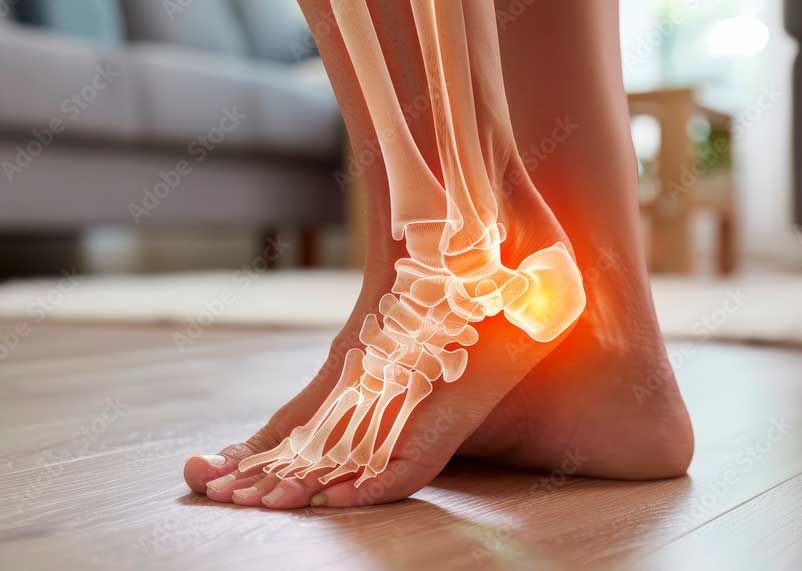

Engrosamiento del Aquiles y delgado plantar.